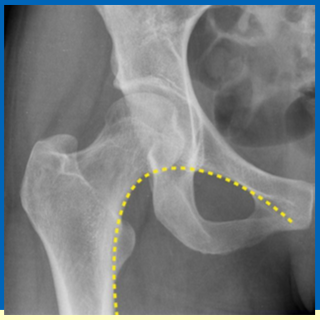

What is indicated by the yellow line and what is the clinical relevance?

Shentons line

Help identify abnormalities at the hip joint, it should be a smooth line as seen on the imagine